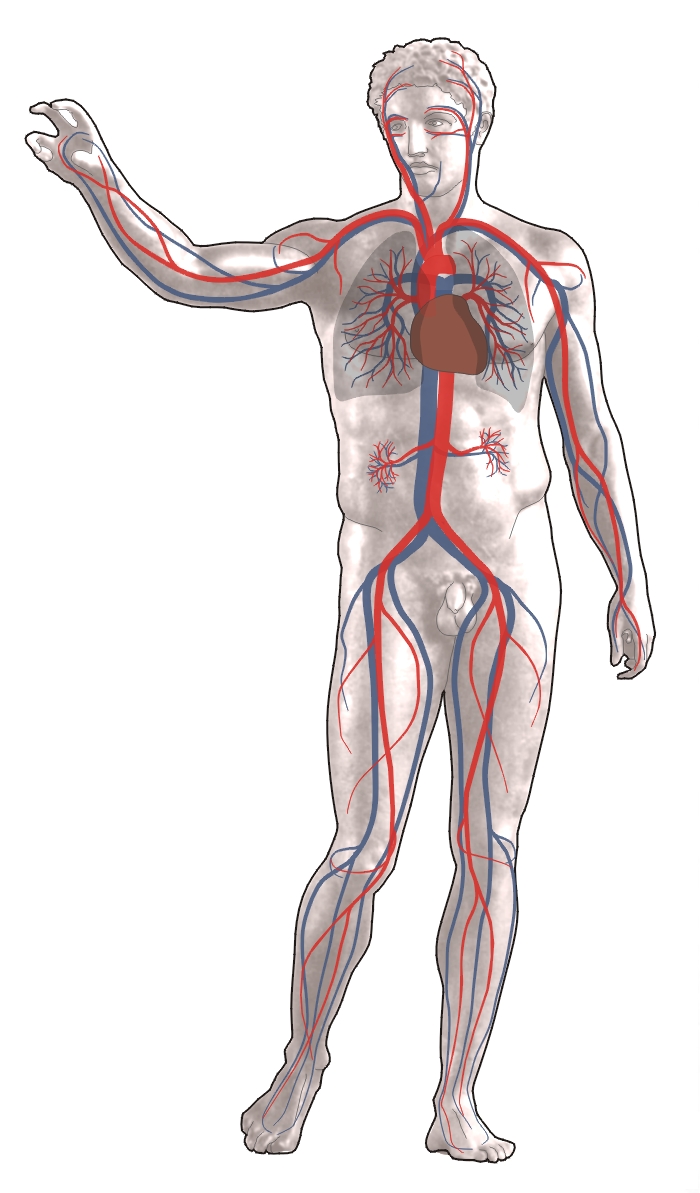

순환계는 심장, 혈관, 혈액으로 구성되어 있으며, 척추동물의 심혈관계는 심장과 혈관으로 이루어져 있다. 순환계는 폐순환과 온몸 순환으로 나뉘며, 폐순환은 우심실에서 폐로 혈액을 보내 산소를 공급받아 좌심방으로 돌려보내는 순환이고, 온몸 순환은 좌심실에서 신체 각 부분으로 산소 공급 혈액을 보내고 대정맥을 통해 탈산소화된 혈액을 우심방으로 되돌리는 순환이다. 인간의 순환계는 폐쇄형이며, 림프계는 순환계의 필수적인 하부 기관계로 간질액을 배출하고 림프를 운반하여 면역계와 협력한다. 순환계는 혈액의 순환을 통해 산소, 영양소, 노폐물 등을 운반하며, 다양한 질병의 원인이 될 수 있다. 일부 무척추동물은 개방 순환계를 가지며, 척추동물과 일부 무척추동물은 폐쇄 순환계를 갖는다. 순환계에 대한 연구는 고대 이집트 시대부터 시작되었으며, 윌리엄 하비의 연구를 통해 혈액 순환의 원리가 밝혀졌다.

순환계는 심장, 혈관, 혈액으로 구성된다.[51] 모든 척추동물의 심혈관계는 심장과 혈관으로 구성되며, 순환계는 폐순환과 온몸순환으로 나뉜다.[52][53][54]

- '''폐순환'''은 우심실에서 산소가 부족한 혈액을 폐로 보내 산소를 공급받아 좌심방으로 돌려보내는 순환이다.

- '''온몸순환'''은 왼쪽 심장에서 신체의 나머지 부분으로 산소가 풍부한 혈액을 보내고 대정맥을 통해 산소가 부족한 혈액을 다시 오른쪽 심장으로 되돌리는 순환이다. 온몸 순환은 대순환과 미세 순환 두 부분으로 나눌 수 있다.

평균 성인의 혈액량은 약 4.7~5.7리터로, 전체 체중의 약 7%를 차지한다.[55] 혈액은 혈장과 혈구(적혈구, 백혈구, 혈소판)로 구성된다. 소화계는 순환계와 함께 작동하여 온몸 순환으로 심장 박동을 유지하는 데 필요한 영양분을 제공한다.[56] 이 외에도 관상동맥 순환, 대뇌 순환, 신장 순환, 기관지 순환이 있다.

인간의 순환계는 폐쇄형 순환계로, 혈액이 혈관망 내에 있다.[57] 영양소는 미세순환계의 작은 혈관을 통해 이동하여 장기에 도달한다.[57]